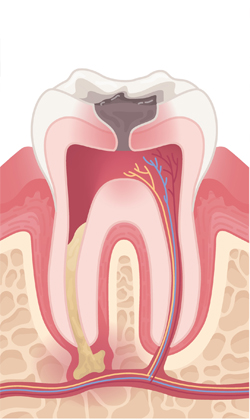

치아 내부 신경이 감염되면 뿌리 끝에 고름이 차는 농양이 생길 수 있습니다. 이로 인해 심한 통증, 부기, 씹기 불편 등이 나타나며 신속한 치료가 필요합니다.

치아 윗부분에 작은 구멍을 만들어 신경관으로 진입할 길을 마련합니다. 이를 통해 내부 염증 부위를 정확히 확인할 수 있습니다.